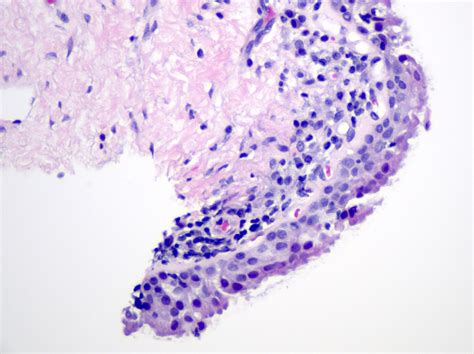

The limbus is a critical structure in the eye, serving as a junction between the transparent cornea and the opaque sclera. It is rich in blood vessels and nerves, which supply the cornea with essential nutrients and oxygen. The limbus is also home to the limbal stem cells, which are responsible for the continuous regeneration of the corneal epithelium. These stem cells are crucial for maintaining the transparency and health of the cornea.

Limbal stem cells are located in the basal layer of the limbal epithelium. These cells have the unique ability to differentiate into various types of corneal epithelial cells, ensuring that the cornea remains clear and free from opacities. The limbus acts as a reservoir for these stem cells, providing a constant supply of new cells to replace those that are lost or damaged. This regenerative capacity is essential for maintaining the integrity of the cornea and preventing conditions such as corneal blindness.